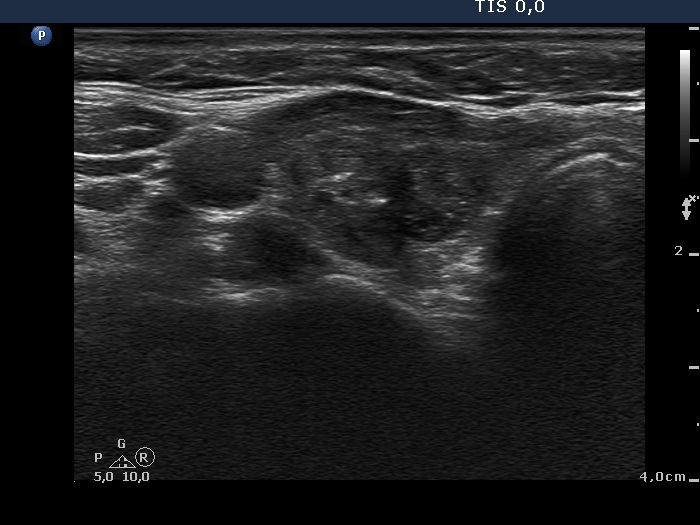

Ethanol sclerotherapy: toxic nodules - Case 2

One year after repeated therapy (ultrasonographic picture 1)

Right lobe, horizontal scan. The nodule presents a dramatic shrinkage. It became evident that the lesion is composed of two smaller nodules.